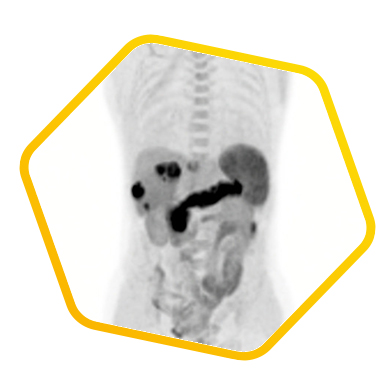

Liver Cancer

Multiple tracers are used to differentiate biochemical properties of liver lesion – Cancer Associated Fibroblast (Ga-68 FAPI uptake)

[C-11] Acetate and [F-18] FDG for hepatocellular carcinoma cellular differentiation (well and poorly differentiated)